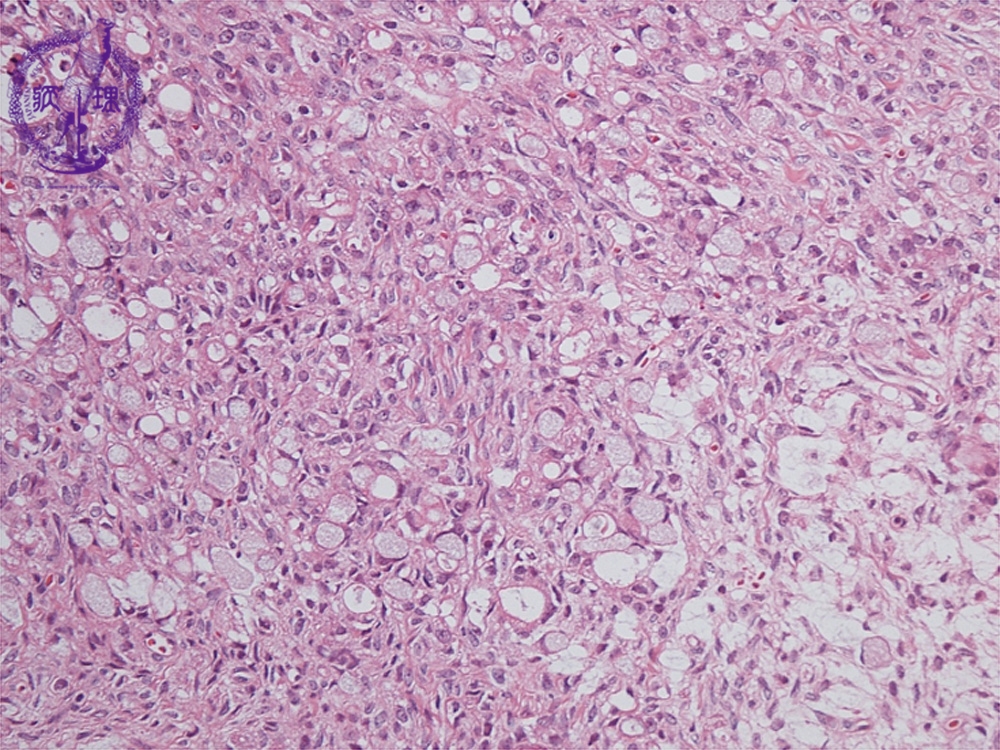

- ★(12)Krukenberg tumor

Histology (HE stain, low power): Signet-ring cell carcinoma proliferated with scattering pattern (light blue). Fibroblasts demonstrated reactive proliferation in interstitium.